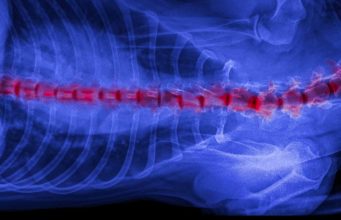

9 Neurological Problems in Dogs with Pictures: Signs, Causes, Treatments

Dogs can suffer from many health problems, including neurological issues which are often worrying for pet owners to deal with.

Knowing how to spot the...